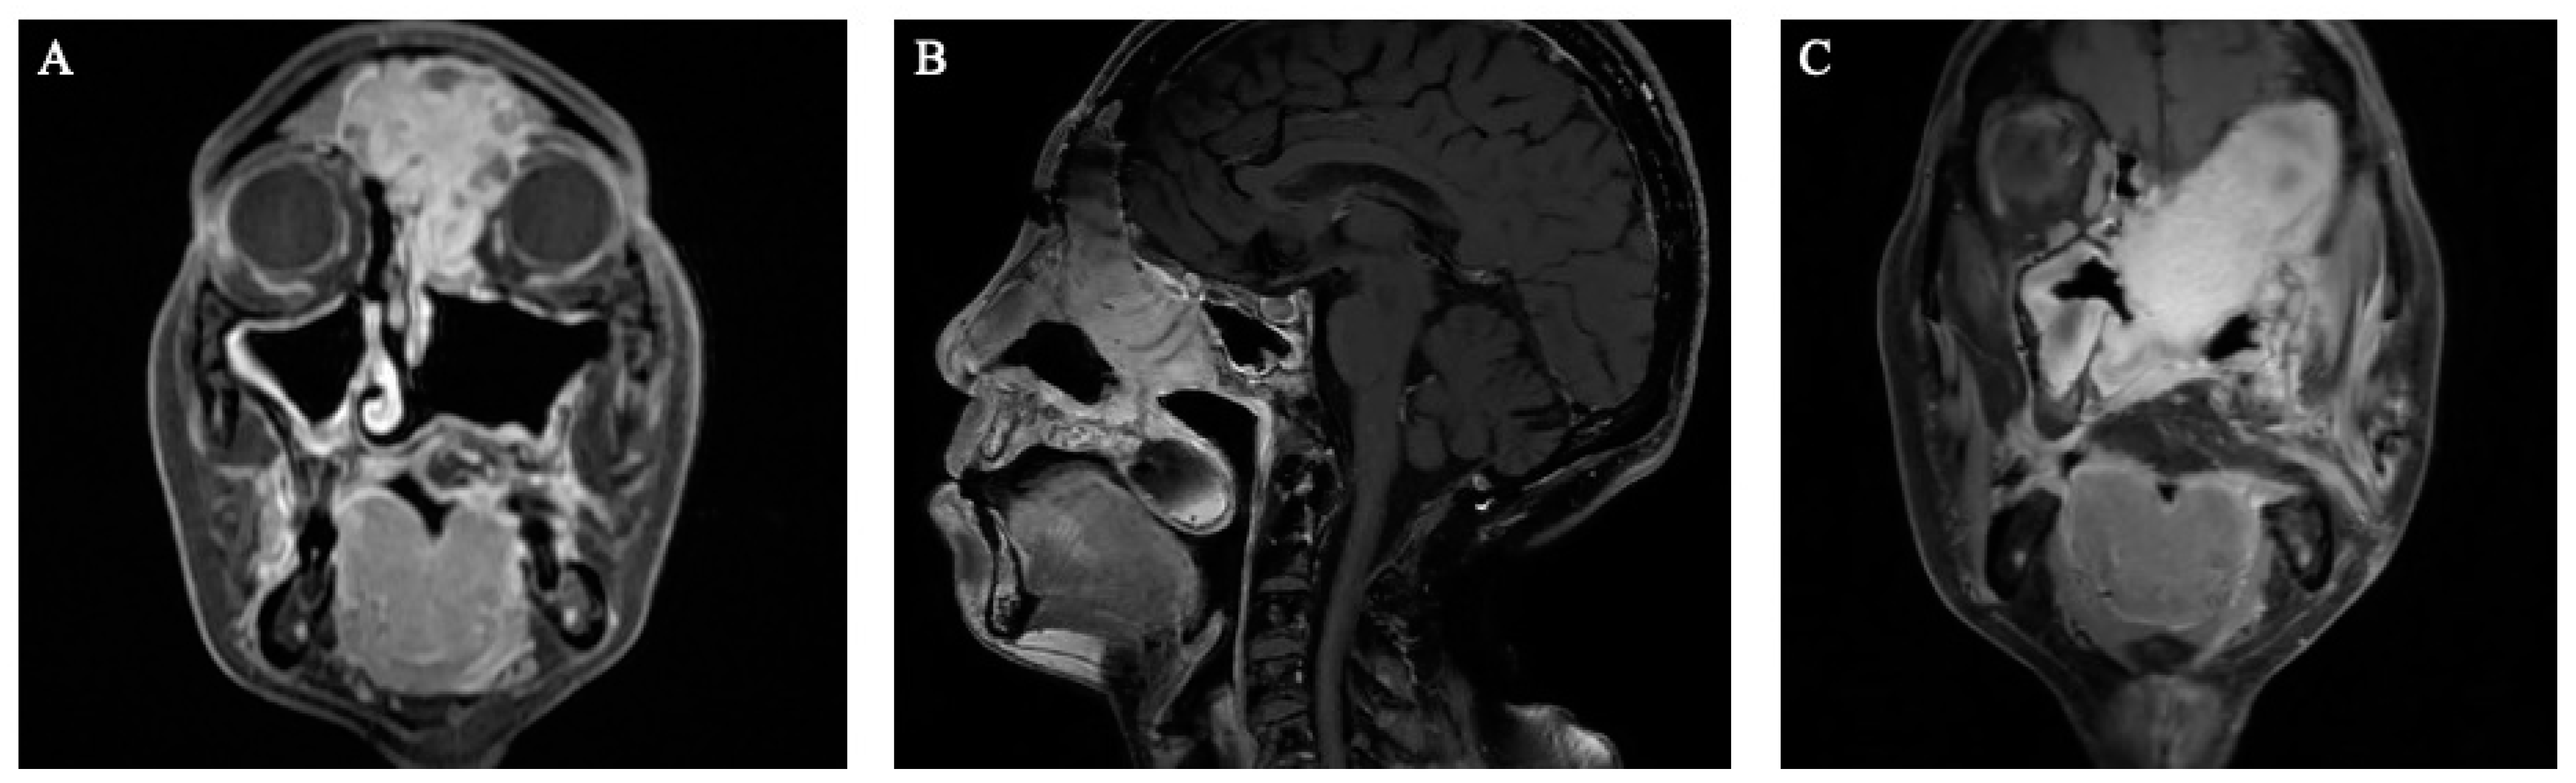

Multi-layer closure techniques are an essential component of skull base reconstruction and have decreased postoperative CSF leak rates to between 5–10% [2]. In patients with large defects and low-flow CSF leaks or patients with high-flow CSF leaks, multi-layer repair is recommended [8]. This often consists of subdural inlay grafts, onlay grafts (non-mucosalized), and a vascularized flap. The types of inlay grafts described include synthetic collagen substitutes, an acellular dermal matrix, temporalis fascia, and fascia lata. Fascia lata or alloplastic material is commonly used for onlay grafts, and particular attention is given to adequately overlapping the graft onto the surrounding bone, removing excess adipose tissue, and ensuring that the surrounding bone is stripped of any mucosa [9]. Figure 1 demonstrates an example of anterior skull base reconstruction with synthetic dura, fascia lata, and pedicled nasoseptal flap.

Figure 1. (A) Preoperative T1 post-contrast coronal image demonstrating a large right sinonasal mass. (B) Intraoperative endoscopic view of the anterior skull base after esthesioneuroblastoma resection. The skull base was reconstructed with a synthetic dura, fascia lata, and a left-sided pedicled nasoseptal flap. (C) Postoperative coronal MRI image demonstrating skull base reconstruction along the resection bed.